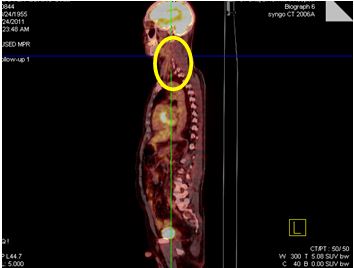

• Chụp PET/CT đánh giá toàn thân trước điều trị: Hình ảnh khối hạch vùng cổ trái kích thước 10x12 cm, tăng hấp thu FDG mạnh. Cơ quan bộ phận khác không thấy tăng hấp thu FDG.

• Hình 1: Hình ảnh khối hạch vùng cổ trái kích thước 10x12 cm, tăng hấp thu FDG mạnh (vòng tròn vàng).